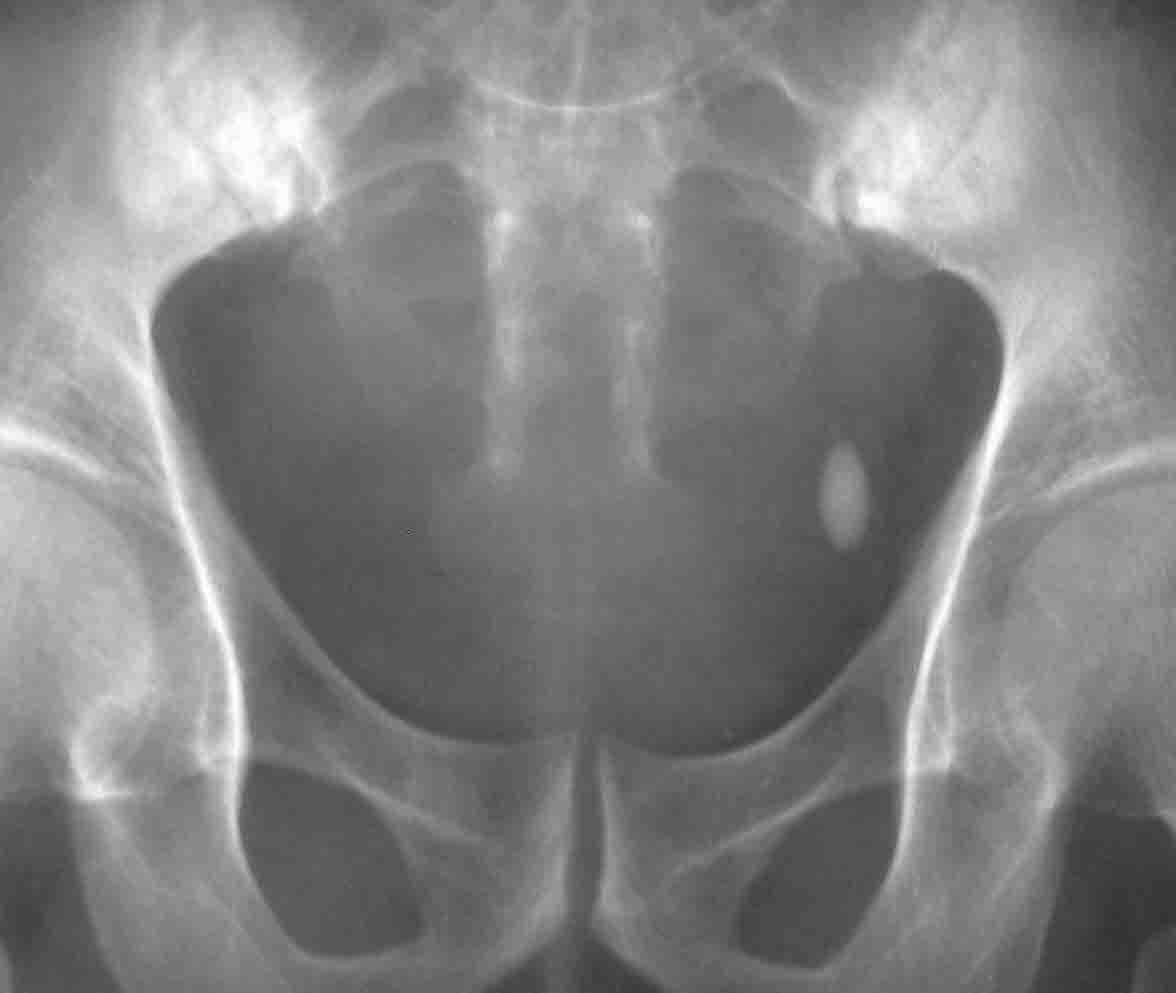

性别:男 60岁,因左侧输尿管末端结石行ivp,上述5张片分别为kub片和7分 15分 30分及120分钟延迟片.

双侧骶髂关节好象有问题

3.双侧骶髂关节病变.

这个ivp是怎么作的7分15分的膀胱区摄片,是不是不用压迫腹带?考虑膀胱憩室,加照双斜位,骶髂关节病变考虑强直性脊柱炎

同意6楼意见+双侧骶髂关节致密性骨炎

收回以前的话,骶髂关节没病,与照片有关